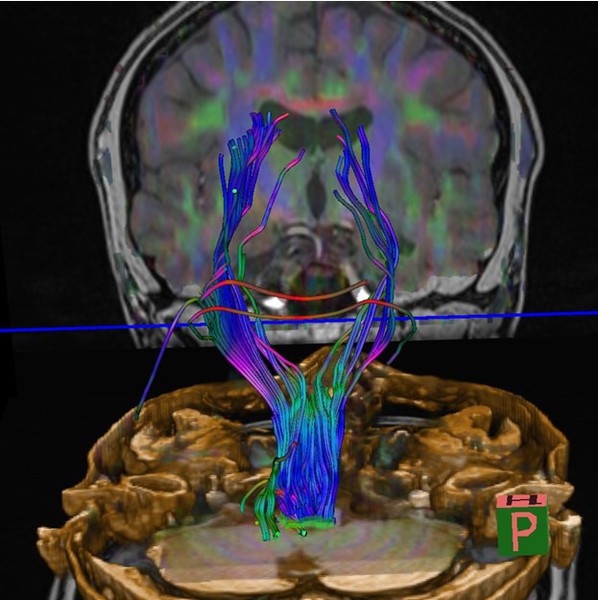

Коннектом мозга: визуализация связей и нейронных путей